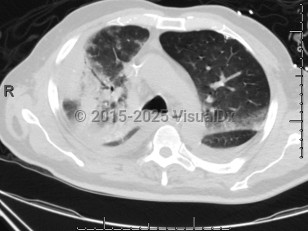

Chlamydophila pneumoniae pneumonia

Chlamydophilia pneumoniae (also known as Chlamydia pneumoniae) is an obligate intracellular bacterium that causes pneumonia.